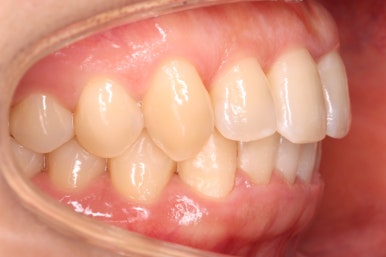

마찬가지로 부산설측교정 키다리아저씨치과에서 처음 내원하셨을 당시의 입안 모습입니다.

어금니쪽은 특별히 이상이 없었고, 위아래 앞니만 삐뚤한 상태였습니다.